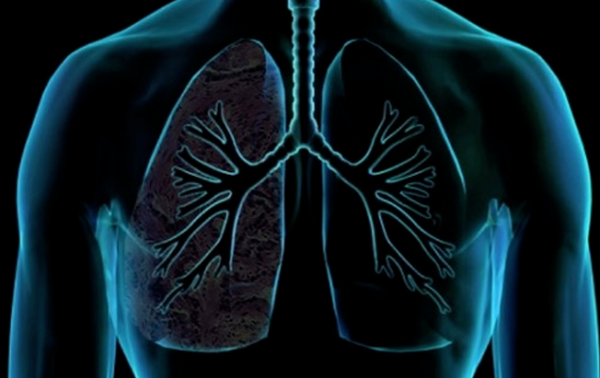

폐암은 국내 암 사망률 1위로, 과거에는 흡연이 폐암의 주요 원인이었지만 최근에는 비흡연자의 폐암 발병이 크게 증가하고 있습니다. 폐암은 오랜 기간 암 사망률 1위를 차지하고 있지만, 의학의 발전으로 생존율이 높아지고 있습니다. 그러나 초기 단계에서 올바르게 관리하는 것이 중요합니다. 폐암의 초기 징후가 무엇인지, 폐암에 좋은 음식은 무엇인지 알아두는 것이 좋습니다.

흡연자와 비흡연자를 비교하면 흡연자는 폐암에 걸릴 확률이 낮게는 15배, 높게는 80배까지 높아질 수 있고, 폐암의 마지막 원인 중 하나이기 때문에 흡연자라면 금연을 하는 것이 정말 좋습니다.